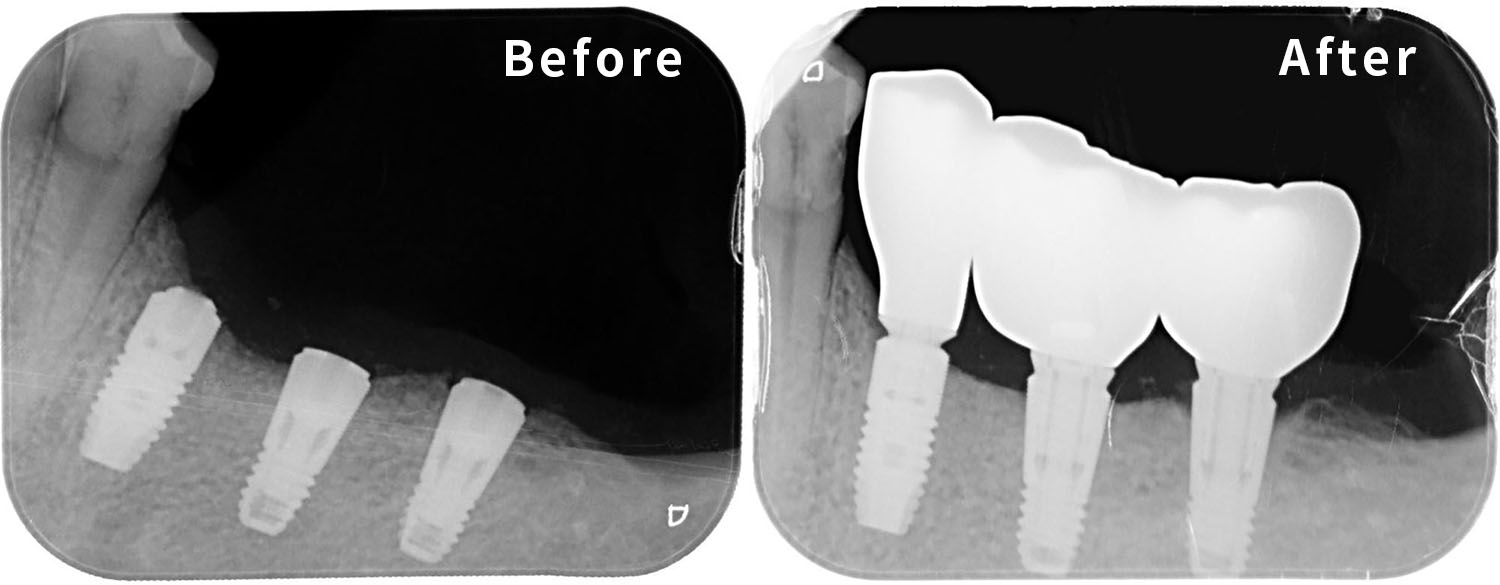

2. 治療方式:All-on-4/6全口重建、舒眠麻醉、導航植牙

▲下顎僅存1顆牙,透過All on 4植入4支植體